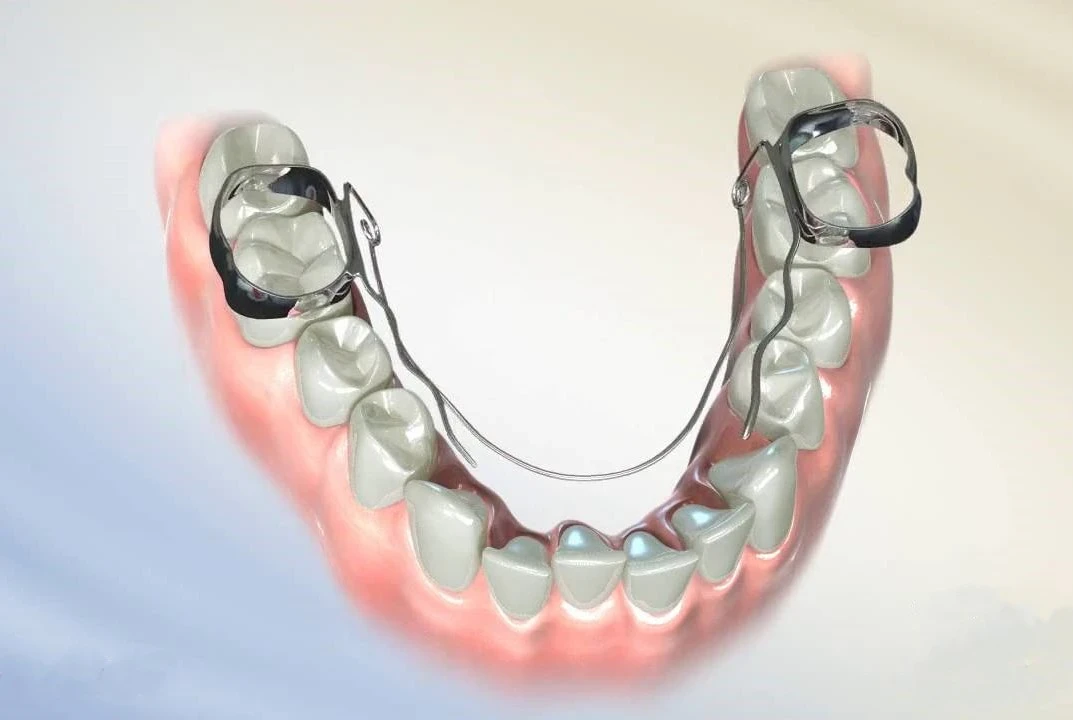

L'orthodontie linguale

La correction invisible par excellence

L’orthodontie linguale se différencie des traitements multibagues traditionnels, du fait de son emplacement : les bagues et les fils sont installés sur la surface interne des dents, du côté de la langue, rendant ainsi le traitement invisible.

C’est pour cela que cette technique d’orthodontie séduit de plus en plus de patients adultes, désireux d’embellir leur sourire sans que personne ne le sache.

Ce traitement n’est pas réservé à l’adulte : le Dr Christophe MAYODE pourra le prescrire à des adolescents, désireux de bénéficier d’un traitement d’orthodontie invisible.

À savoir :

À la fin de chaque traitement d’orthodontie linguale, le Dr C. MAYODE prévoit une double contention, incluse dans le traitement, afin de garantir la stabilité de ce dernier dans le temps.